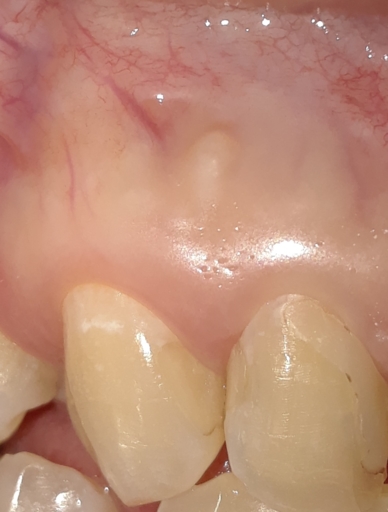

My tooth has an abscess so an endodontist started my root canal, drained it and put antibiotic inside and a temporary filling. When I went back to finish it he said it was still draining and I clearly still had the abscess on my gums but went on to seal the root anyway. Should he have better cleared the infection before finishing the procedure?

My tooth has an abscess so an endodontist started my root canal, drained it and put antibiotic inside and a temporary filling. When I went back to finish it he said it was still draining and I clearly still had the abscess on my gums but went on to...